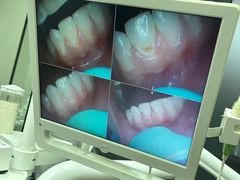

• 牙博士口腔品牌连锁(杨浦店)

• -牙博士口腔品牌连锁(杨浦店)